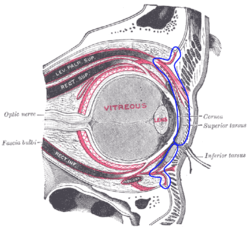

The right eye in sagittal section, with structures of the orbital septum within blue markings. | |

The orbital septum (Palpebral fascia) is a membranous sheet that acts as the anterior boundary of the orbit. It extends from the orbital rims to the eyelids. It forms the fibrous portion of the eyelids.[1]

In the upper eyelid, the orbital septum blends with the tendon of the levator palpebrae superioris, and in the lower eyelid with the tarsal plate.[2]

When the eyes are closed, the whole orbital opening is covered by the septum and tarsi. Medially it is thin, and, becoming separated from the medial palpebral ligament, attaches to the lacrimal bone at its posterior crest. The medial ligament and its much weaker lateral counterpart, attached to the septum and orbit, keep the lids stable as the eye moves.[3]